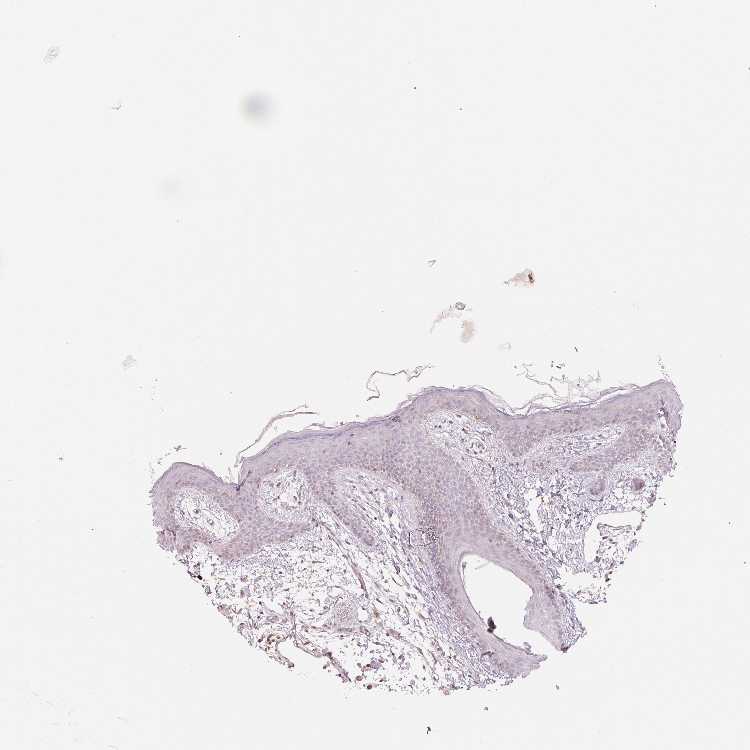

OR13C3